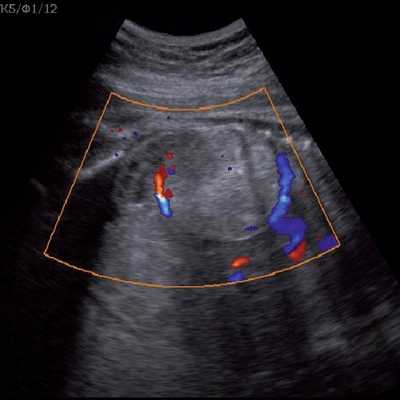

Цветовое допплеровское картирование помогает идентифицировать питающий опухоль сосуд, отходящий непосредственно от аорты, однако такой единственный сосуд может и не визуализироваться [13].

Под диафрагмой справа визуализировалось гиперэхогенное опухолевидное образование несколько неоднородной солидной структуры, с четкими ровными контурами, размером 50x38x35 мм. К нижнему полюсу данного образования прилежала правая почка, имеющая нормальные размеры, форму и структуру. Нижняя полая вена была смещена кпереди и влево. Обращала на себя внимание выраженная гепатомегалия, причем структура печени не была однородной. Она содержала множественные гиперэхогенные включения размерами до 17 мм, окруженные тонким гипоэхогенным периферическим ободком. Цветовое допплеровское картирование(ЦДК) демонстрировало интенсивную периферическую васкуляризацию опухоли (рис. 1-3).

Рис. 2. Кровоток в нейробластоме плода. Цветовое допплеровское картирование. Отчетливо виден питающий сосуд, огибающий образование по его периферии. К нижнему полюсу образования прилежит интактная почка плода.

Рис. 3. Метастазы в печени плода. Поперечное сечение брюшной полости плода. Гепатомегалия. В структуре печени плода определяются округлые включения несколько повышенной эхогенности (стрелки), с гипоэхогенным ободком - метастазы.